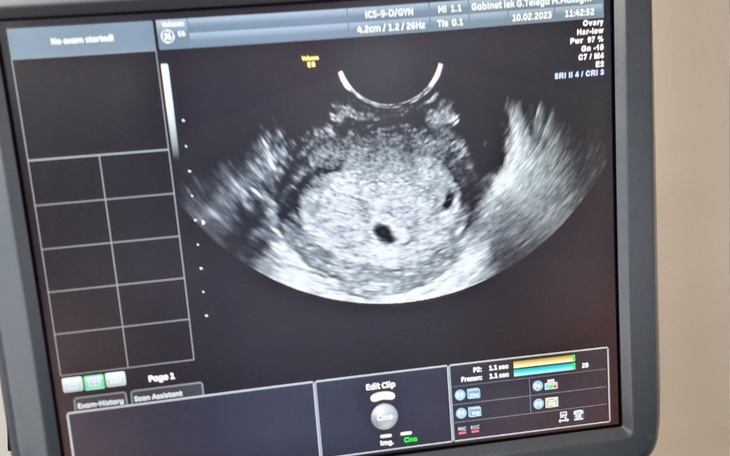

Witam przyjechalismy do polski wraz z zoną filipinką ,ona nie moze pracować . Zaszła w ciąże lecz nie ma polskiego ubezpieczenia jestesmy w kropce potrzebujemy zebrac okolo 10 tysiecy na porod w polsce zeby nie deportowali mojej zony i dziecka ...